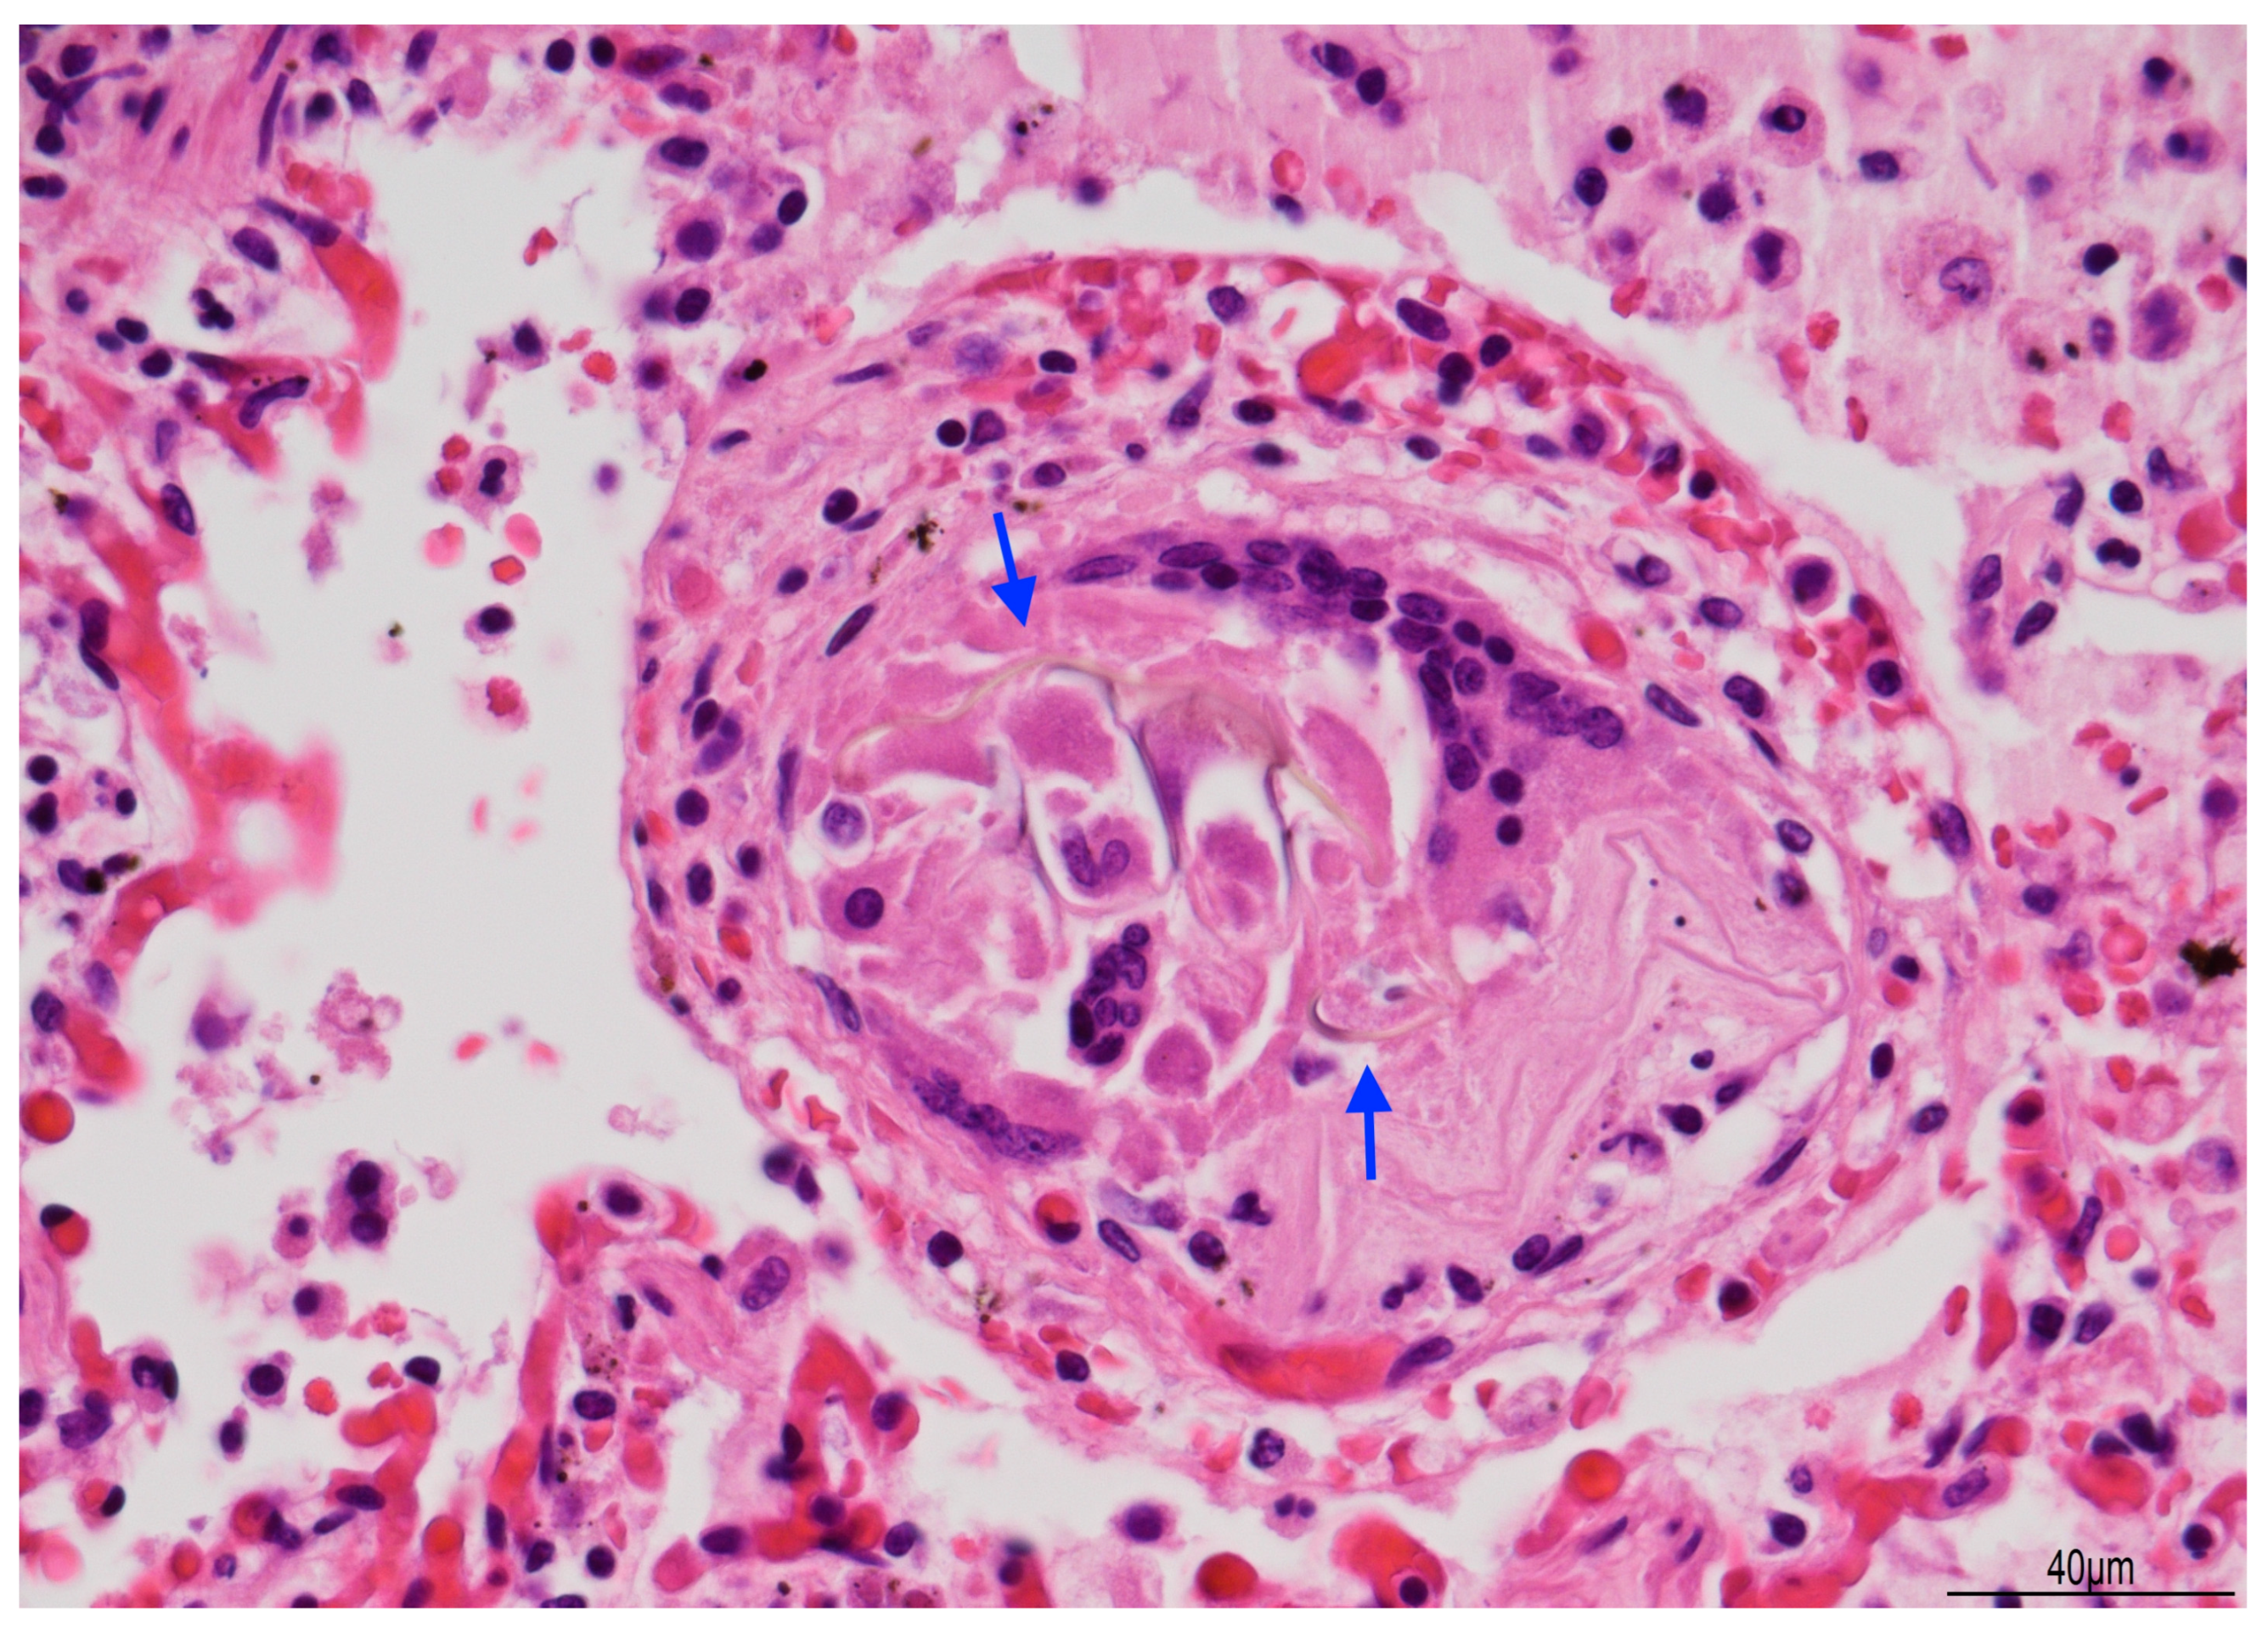

Lung histology revealed acute exudative pneumonia with abundant neutrophils, fibrin deposition, intra-alveolar hemorrhage, bacterial colonies (cocci), abundant lipid-laden macrophages (compatible with early lipoid pneumonia), and focal foreign-body giant cell reaction to aspirated material (Figure 7, Figure 8 and Figure 9). Histochemistry for PAS, PAS-D, and Grocott were performed to rule out fungal colonization and resulted negative.

Figure 9. Giant cell reaction to foreign body: brown fibers (arrows), likely due to aspirated material, were seen within multinucleated giant cells (Hematoxylin and Eosin, 40 HPF).